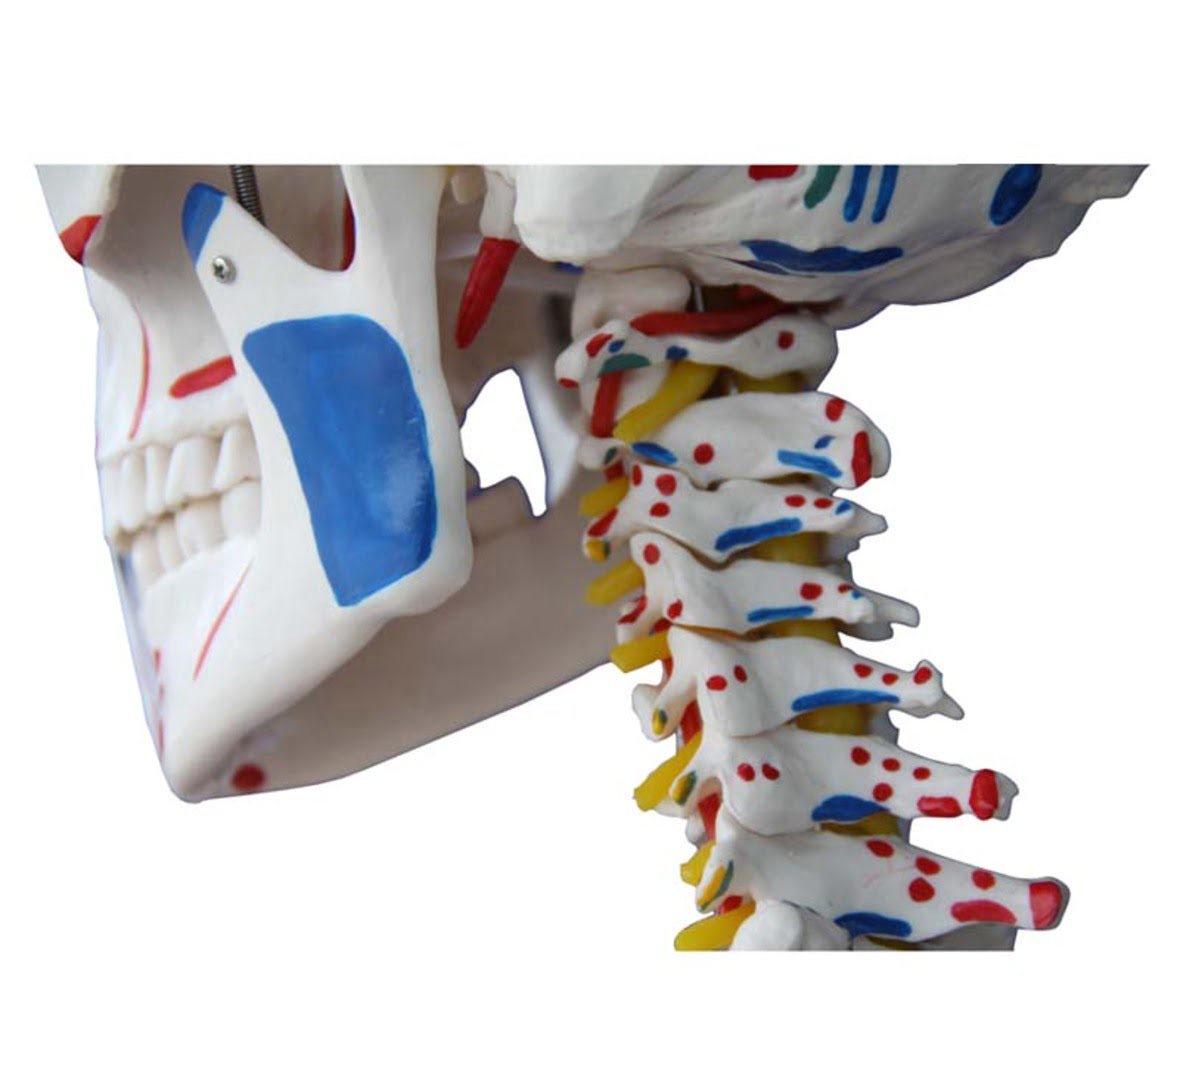

Skeleton with Muscles and Ligaments

Skeleton with Muscles and Ligaments

Τhis model is painted to show the muscles and ligaments. The left side of the skeleton shows the points of origin (red) and the points of insertion (blue) of the muscles.

SPECIFICATIONS

Size: 180cm (Life Size)

Material: PVC

Weight: 14Kg

Base is included.

Skeleton with Muscles and Ligaments

Skeleton with Muscles and Ligaments